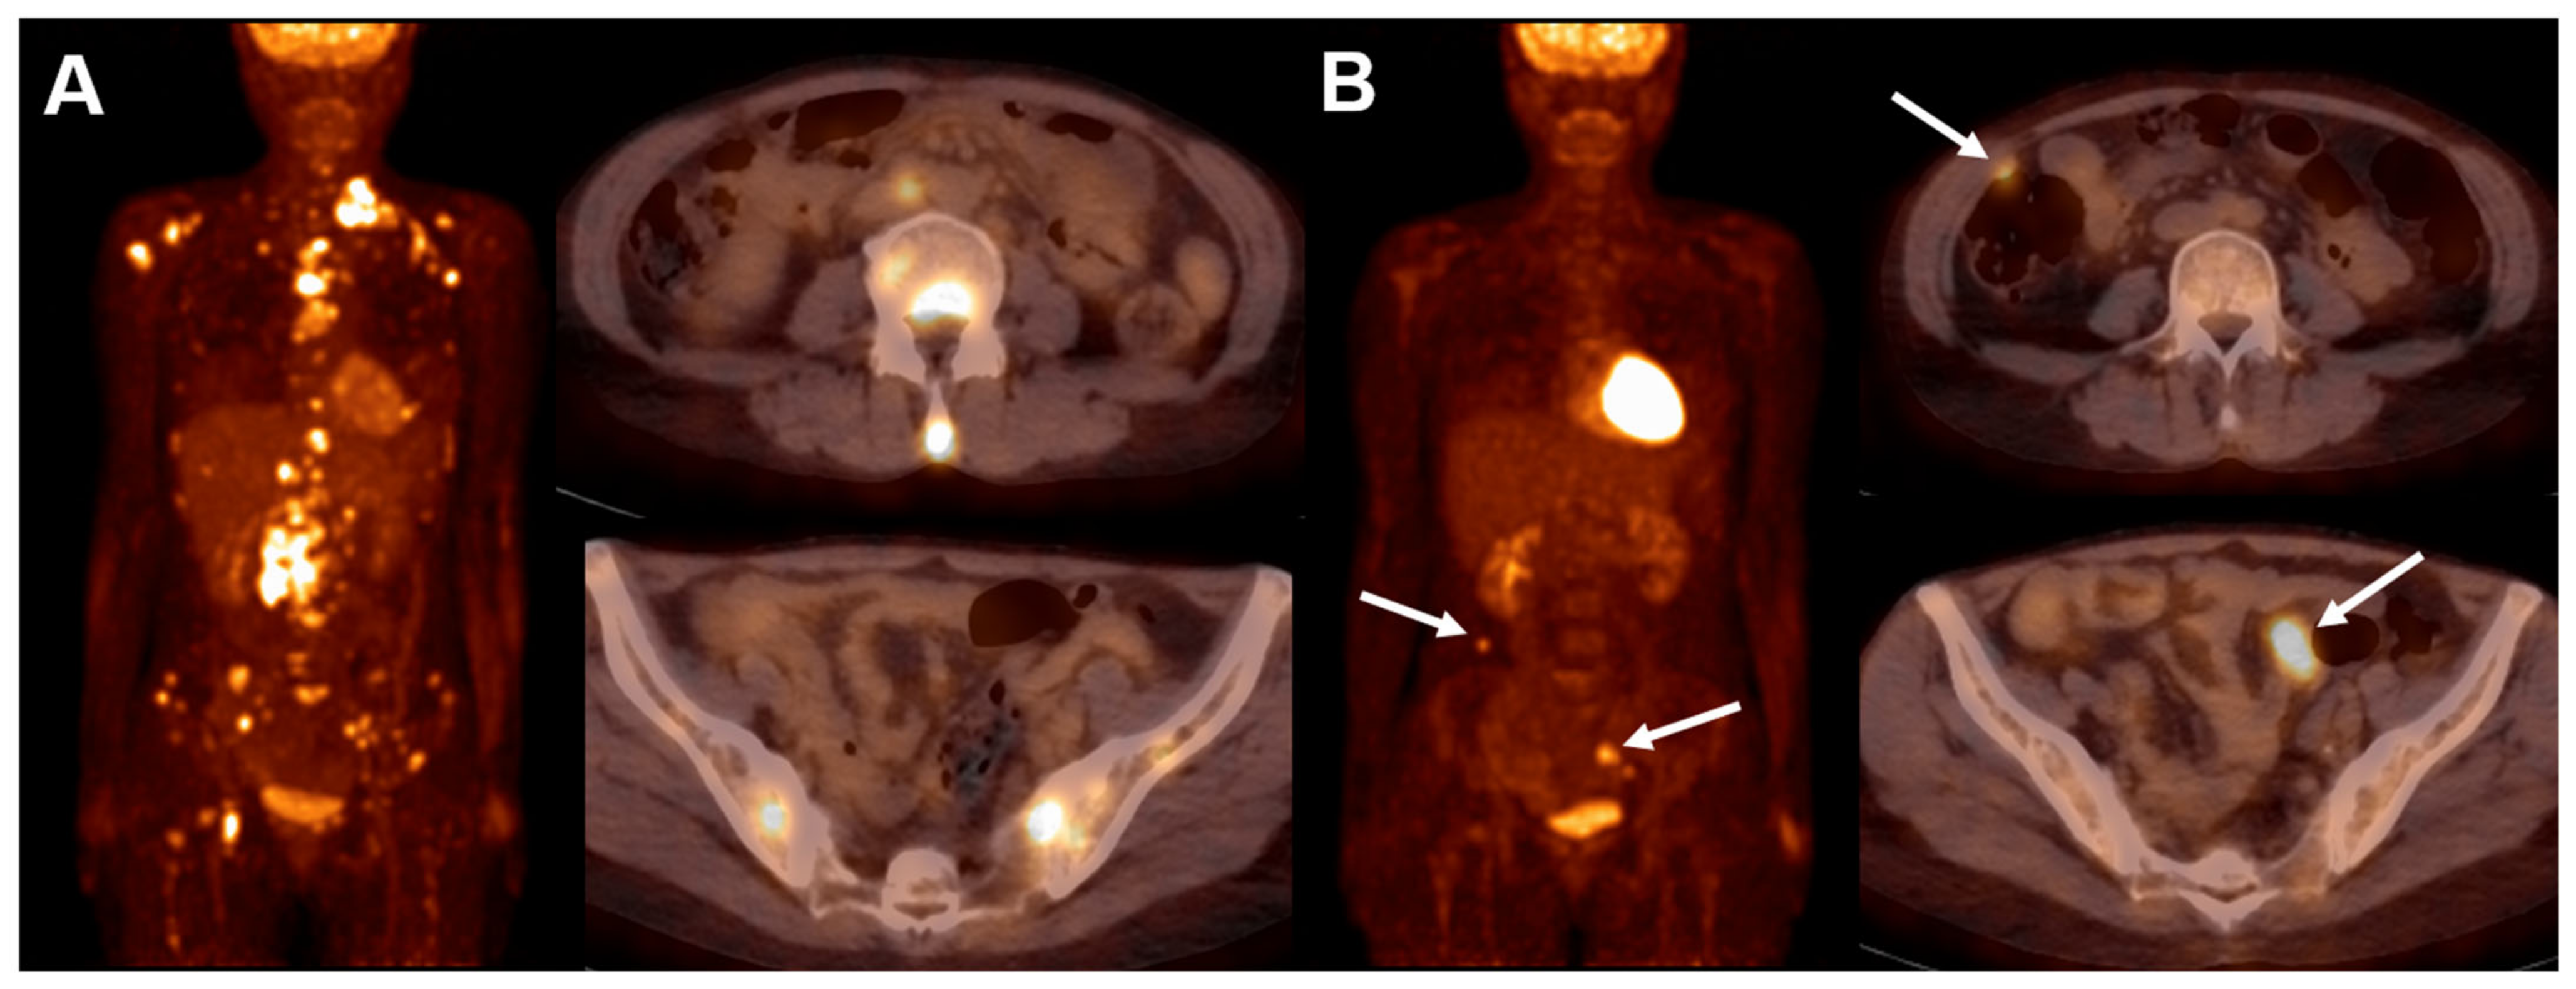

- Galtier, J.; Vercellino, L.; Chartier, L.; Olivier, P.; Tabouret-Viaud, C.; Mesguich, C.; Di Blasi, R.; Durand, A.; Raffy, L.; Gros, F.X.; et al. Positron emission tomography-imaging assessment for guiding strategy in patients with relapsed/refractory large B-cell lymphoma receiving CAR T cells. Haematologica 2023, 108, 171–180. [Google Scholar] [CrossRef]